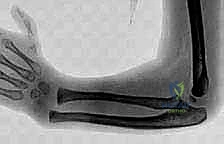

- Reduction and Stabilization of the Distal Radioulnar Joint Following Galeazzi Fractures